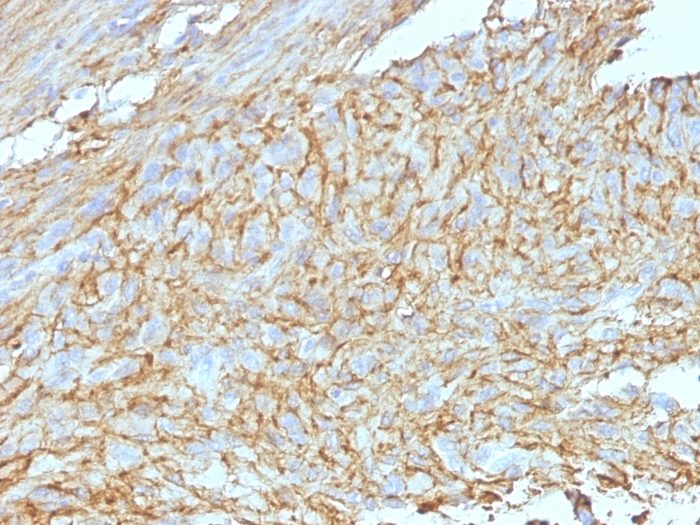

Immunohistochemistry (Formalin/PFA-fixed paraffin-embedded sections) - Anti-TMEM16A antibody [EPR10643(2)] (AB190803)

Immunohistochemical analysis of paraffin embedded Human gastrointestinal stromal tumor tissue sections labeling TMEM16A using ab190803 at a 1/500 dilution. A ready to use HRP Polymer for Rabbit IgG was used as the secondary antibody. Hematoxylin counterstain.

Perform heat mediated antigen retrieval with Tris/EDTA buffer pH 9.0 before commencing with IHC staining protocol.